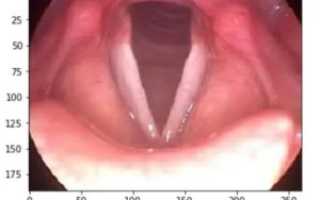

Как проверить голосовые связки

Гортань – это часть дыхательной системы, которая соединяет глотку с трахеей и содержит ой аппарат – ые связки.

В свою очередь, ые связки – это складка в слизистой оболочке гортани, в которой находятся ая связка и ая мышца.

Когда Вы хотите что-то сказать, под действием выдыхаемого воздуха из легких, ые связки натягиваются и колеблются, создавая различные звуки. Кроме этого, ые связки служат барьером для вдыхаемых посторонних частиц.

Обследование гортани и ых связок строится по нескольким направлениям:

• Оценка строения гортани и ых связок

• Исследование ой функции

Перед тем, как приступить к осмотру внутренней поверхности гортани и ых связок, врач может оценить состояние органов стандартными методами (внешний осмотр, пальпация). Как правило, врач может заметить патологию (хриплость, осиплость, гнусавость голоса), не прибегая к инструментальным методам исследования.

Основным методом исследования гортани и ых связок является ларингоскопия. Наша клиника может предложить Вам выполнить прямую и непрямую ларингоскопию. Выбор метода исследования осуществляется врачом и зависит от целей диагностического поиска.

Ларингоскопия – это исследование гортани и ых связок с помощью специальных медицинских зеркал (непрямая ларингоскопия) или директоскопа.

Преимущество прямой ларингоскопии в том, что она позволяет проводить различные лечебные иили диагностические манипуляции в гортани.